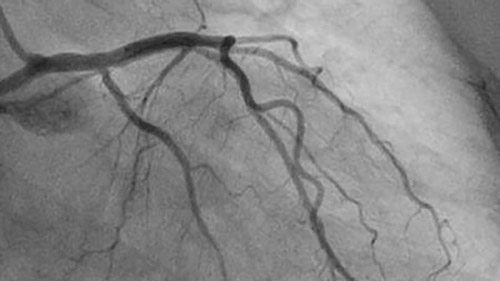

AlluraClarity family of X-ray systems with ClarityIQ technology delivers superb image quality at 50% dose reduction, helping to minimize patient and staff exposure. You can manage low dose levels to see what you must, without changing the way you work.